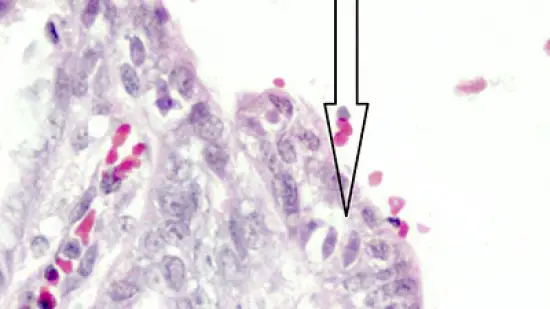

O que são os organismos (indicados pela seta) que há dentro da mucosa do intestino delgado deste leitão com diarreia?